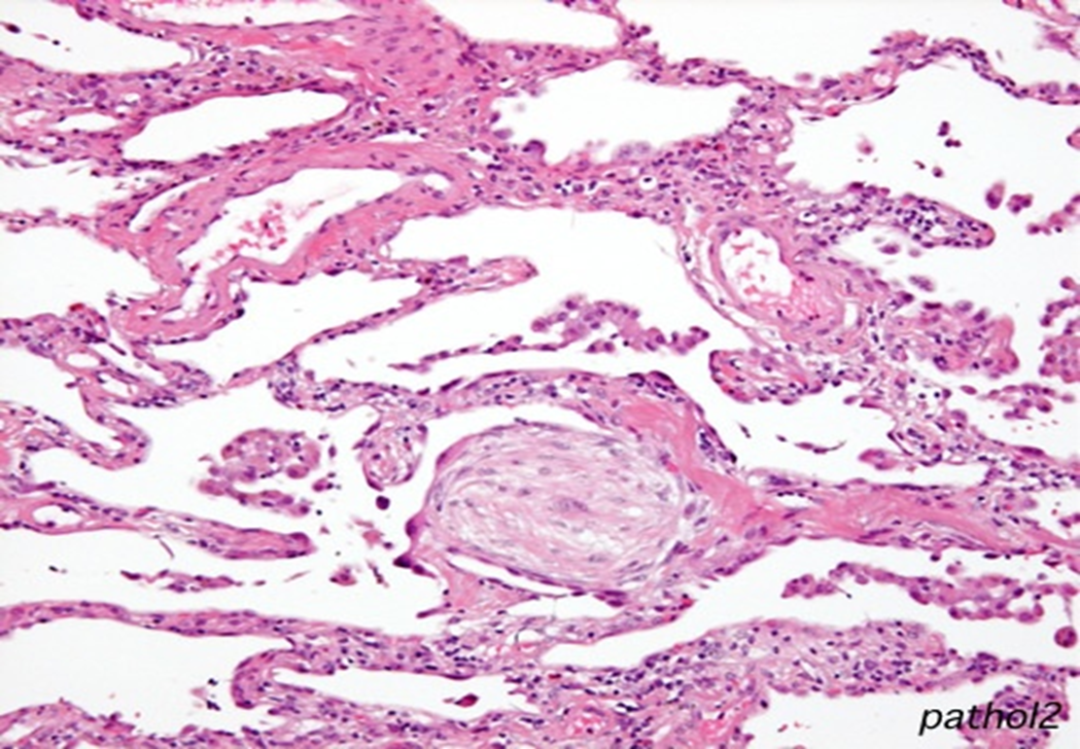

在周围的肺泡间隔存在以单核细胞、淋巴细胞浸润为主的炎性渗出,肺泡间隔增厚,可伴或不伴终末和呼吸性细支气管内结缔组织肉芽栓的形成;肺结构往往正常;镜下病变均匀一致。

图片

注:肺泡内、肺泡管、呼吸性细支气管及终末细支气管腔内有息肉样肉芽组织形成。